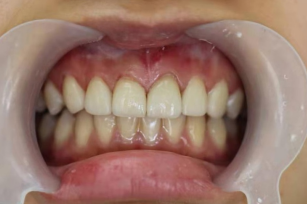

患者,女,20岁。主诉:“因对牙齿颜色及形态不满意,要求修复。”

术后照片

瓷贴面通过酸蚀粘接在完好的、预备过的釉质上,具有更好的粘接强度、颜色稳定性和美观效果。